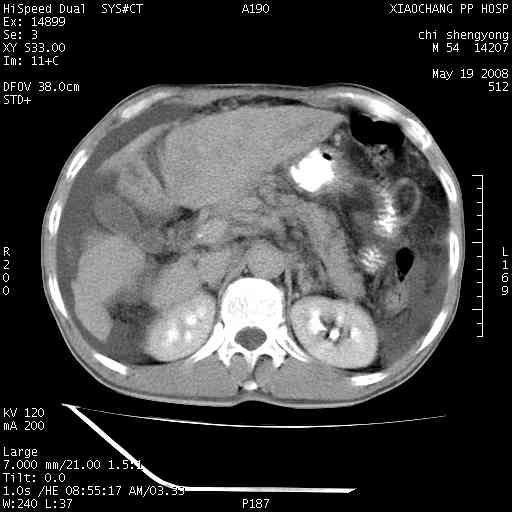

以下是引用zjzjr在2008-5-21 10:52:00的发言:[br]肝左叶巨块型肝癌伴门静脉左支瘤栓形成.肝硬化、腹水,胃底静脉曲张,脾术后改变。

以下是引用随光逐影在2008-5-21 16:20:00的发言:[br]1)肝左叶肝癌伴门静脉左支瘤栓形成,腹膜后淋巴结转移。2)肝硬化、腹水、胃底静脉曲张。3)胆囊炎。4)脾脏缺如,为切除术后所致。